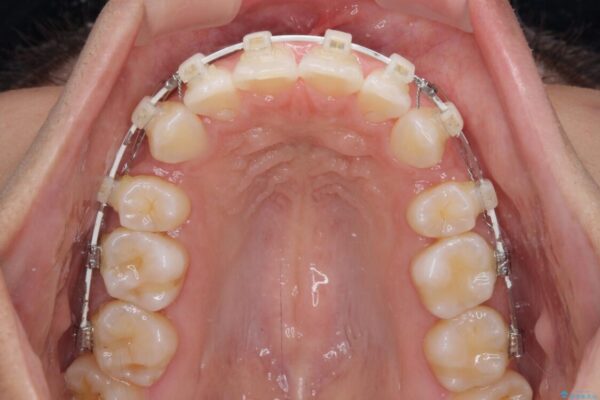

治療途中

• 抜歯矯正で唇を閉じやすく 目立たないワイヤー装置 治療途中画像